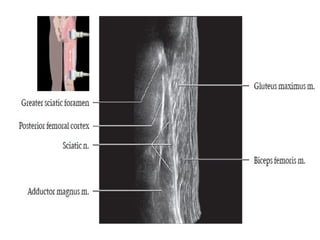

• Crosses over superior gemellus, obturator internus, inferior

gemellus muscles.

• It is deep to long head of biceps femoris muscle.

• Branches arising in thigh:

- Articular to hip,

- Nerves to hamstring muscles

MRI

 T1 or PD help distinguish fluid in vessels from

nerves.

 Correlate with fluid-sensitive sequences.

 Fat fascicles are especially prominent in

sciatic nerve.

04/29/2025 55

• The abundant fat around the fascicles and the nerve itself

makes these structures clearly visible on T1-weighted images.

• Normal fascicular shape was defined as clustered similar-sized

rounded structures on T1 MR images.

04/29/2025 56

• The normal nerve shows a fascicular appearance.

• It has signal intensity from isointense to minimally

hyperintense with respect of the adjacent muscle.

• The perineural fat tissue has a homogeneous signal and a

separation plane with the adjacent structures.

04/29/2025 57